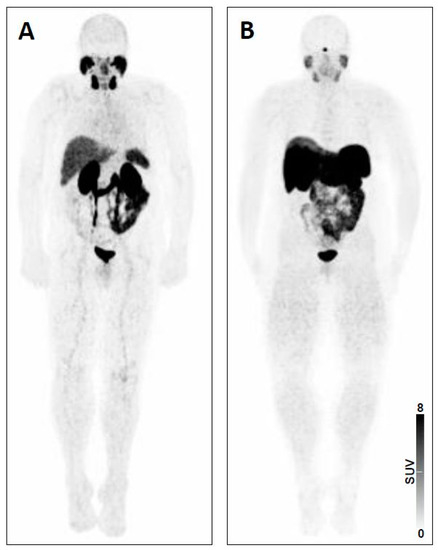

| 5 | - Intense uptake in a liver lesion with definitive findings on conventional imaging [20] | - Extensive metastatic PC with diffuse osseous metastatic disease and intense radiotracer uptake (“superscan“ on PSMA-PET/CT) [19] | |